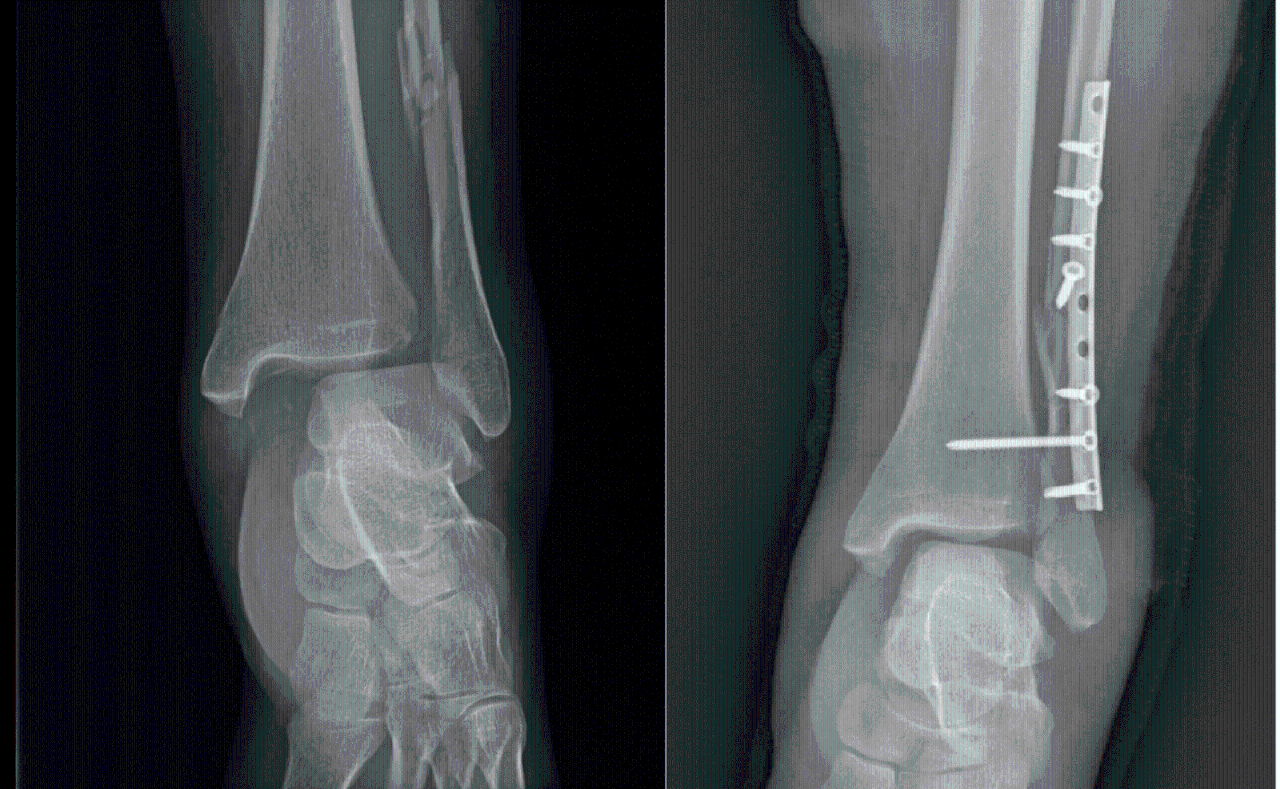

Структура и анатомия синдесмоза: научные иллюстрации